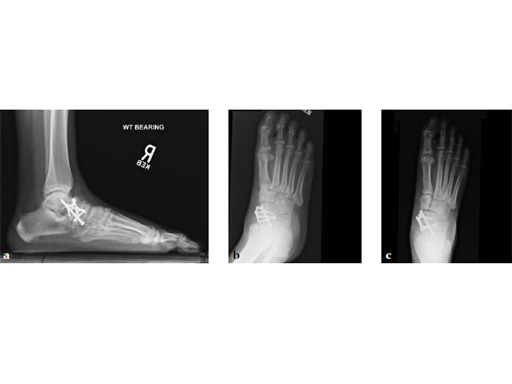

Case 3: First TMT fusion plate

A 48-year-old woman, with hallus valgus and hypermobile medial column, also resulting in pes plano abductovalgus (flatfoot).

Case provided by Andrew Sands, New York, New York, USA

Surgery consisted of first TMT and intertarsal corrective osteotomy plus fusion with movement of the first MT lateral and plantar. This corrects the hallus valgus as well as the PPAV (and stabilizes the medial column).